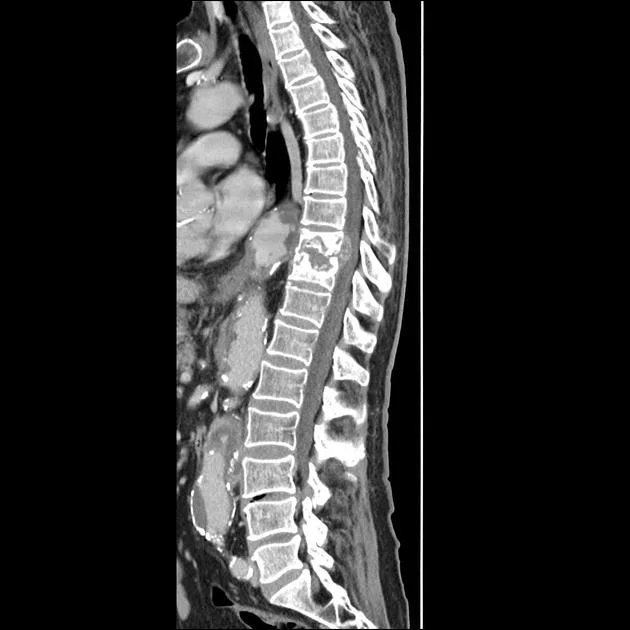

Diagnosis involves clinical evaluation, imaging tests like X-rays, MRIs, or CT scans, blood tests for inflammation markers (ESR, CRP), and tissue biopsy to confirm the presence of TB bacteria in the affected vertebrae.